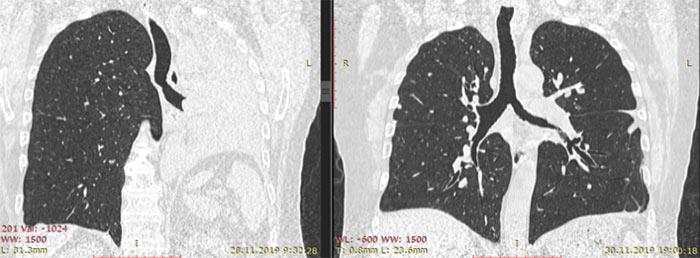

Запал легких